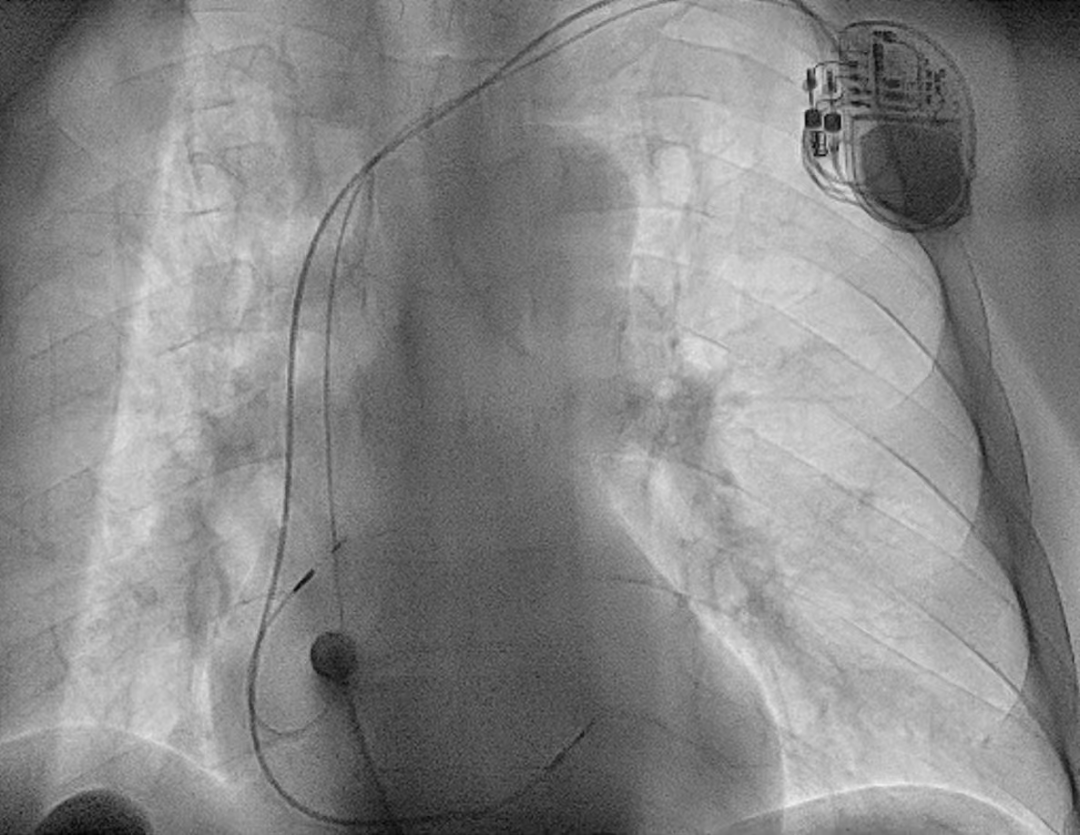

患者李军(化名)因胸痛胸闷一日入住我院CCU科,临床诊断为不稳定型心绞痛、冠状动脉性心脏病、病态窦房结综合征。经过术前讨论决定为患者在局麻下行双腔永久起搏器植入术。科室团队全面评估患者心律、心房传导与心脏结构,精准制定个体化手术方案;术中凭借丰富起搏介入经验与精细操作,顺利将电极精准定位至Bachmann束区域,完成起搏参数测试与系统植入。术后患者心律规整、双房同步性良好,恢复顺利,充分体现该术式的安全性与有效性。术后一个月程控随访显示患者起搏器参数正常,起搏功能良好。

正位 左前斜